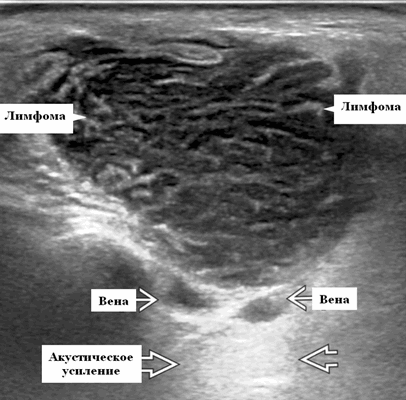

- Узловая неходжкинская лимфома (НХЛ): одиночные или множественные увеличенные яйцевидные внутрипаротидные лимфатические узлы, которые на УЗИ гомогенно гипоэхогенны по отношению к паренхиме околоушной железы, эхо-картина сетчатая. Заднее акустическое усиление. Выраженная внутриузловая гиперваскуляризация

Серошкальное УЗИ. Узловая НХЛ. Одиночные или множественные увеличенные яйцевидные внутрипаротидные лимфатические узлы. Гомогенно гипоэхогенный по отношению к паренхиме околоушной железы. Сетчатый эхосигнал. Заднее акустическое усиление. Первичная паренхиматозная НХЛ. Рассеянный, неоднородный эхосигнал; нечеткие, гипоэхогенные, похожие на опухоль участки. В пунктате внутрикистозная или паренхиматозная кальцификация из-за конечной стадии воспалительного изменения. Небольшие кистозные области образуются из-за сдавления терминальных протоков лимфоидной гипертрофией. Множественные небольшие гипоэхогенные участки (представляют собой лимфоидные агрегаты), разбросанные на фоне ткани слюнной железы. Изменения могут имитировать хронический сиалоаденит и диагноз часто ставится при биопсии. На УЗИ необходимо искать аналогичное поражение других слюнных и слезных желез, фон синдром Шегрена, BLEL. Может иметь или не иметь перипаротидную и шейную лимфаденопатию

- Используя современные датчики высокого разрешения, несмотря на их солидную природу, лимфоузлы НХЛ имеют тенденцию к заднему усилению

- При ультразвуковом сканировании лимфоузлы неходжкинской лимфомы показывают интранодальный ретикулярный / микронодулярный рисунок с использованием более новых датчиков с высоким разрешением

Обычно на УЗИ это гипоэхогенный лимфоузел по сравнению с соседними мышцами и ранее описывалось как псевдокистозные узлы с задним усилением. При использовании более старых преобразователей внутренние эхосигналы в узлах были очень низкими, почти анэхогенными, напоминающими кисту. Используя современные датчики высокого разрешения, несмотря на их солидную природу, мы видим, что узлы НХЛ имеют тенденцию к заднему усилению. Равномерная клеточная инфильтрация внутри узлов создает меньше границ между структурами и облегчает прохождение ультразвука. Это, в сочетании с низкой внутренней эхогенностью, приводит к так называемому псевдокистозу. Лимфоузлы неходжкинской лимфомы показывают интранодальный ретикулярный или микронодулярный рисунок с использованием более новых преобразователей высокого разрешения